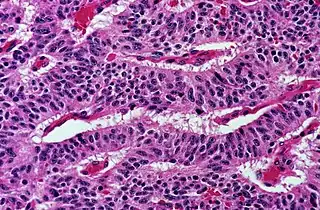

- Solid: More or less the same cell type throughout, with no spaces between, and no other particular pattern.

- Pleomorphic when having different sizes and shapes. This often correlates with an increased nucleus to cytoplasm ratio. These features generally indicate malignancy.